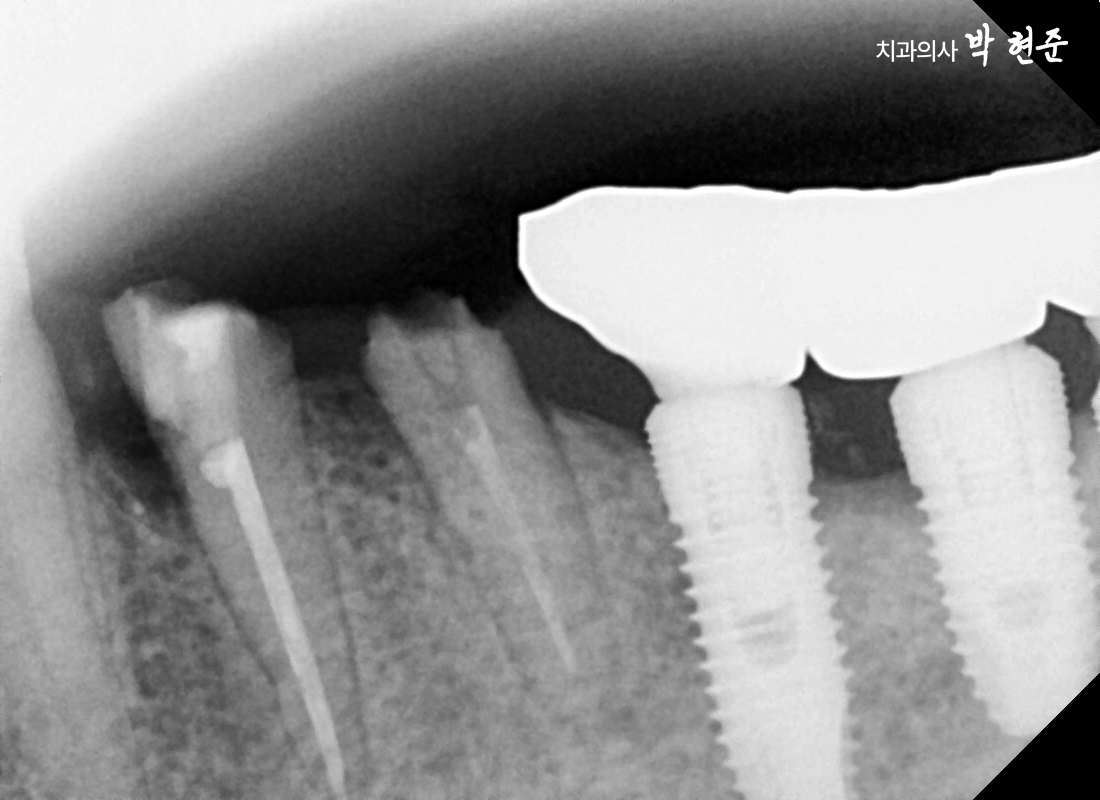

1. 왼쪽 아래 작은 어금니 파절

2024.09.14

구강을 살펴보면

왼쪽 아래 두 개의 작은 어금니가

파절되었습니다.

치아는 머리(치관) 부분과

뿌리(치근)로 나뉘는데

이 케이스에서는 치관의 전부가

깨져버린 것이죠.

자세히 살펴보면

치아 안으로 무언가 채워져 있는 게

보이시나요?

이것은 과거에 신경치료를 받았다는 의미인데요,

신경치료를 하게 되면

자연치 내부에서

혈액과 영양분을 공급하는

치수가 사라지기 때문에

시간이 지나면서 점점 푸석푸석해지고

약해지게 됩니다.

그러다 보니 이를 보호하기 위해

크라운을 꼭 씌워야 되는데,

아무리 크라운을 잘 씌워두더라도

시간이 지나면서

그 틈새로 이차 우식이 생기거나

저작력을 강하게 받게 되면

상대적으로 약한 부위를 기준으로

이가 부러지게 될 수 있습니다.